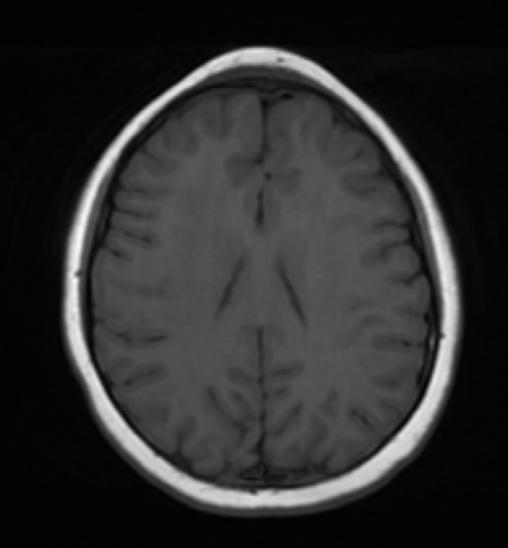

67 Cefalea… occhi aperti

Giuseppe Paviglianiti, Elisa Costantini, Gianluca Coscia, Floriana Di Marco, Vittorio Messina, Domenico Cipolla, Angelo Spataro